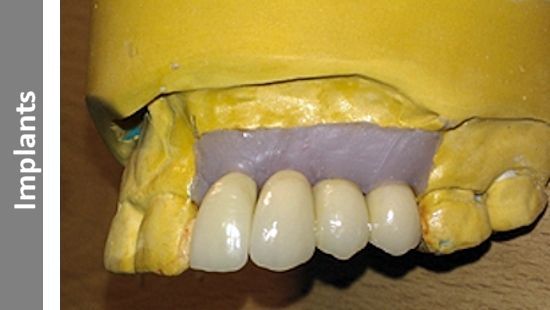

Sky Dental Ceramics is a professional service creating dental restorations that have a truly natural look.

All of our dental restorations are produced by registered Dental Technicians from our small, dedicated lab.

Our reputation and service is based on over 25 years of knowledge, skills and experience.